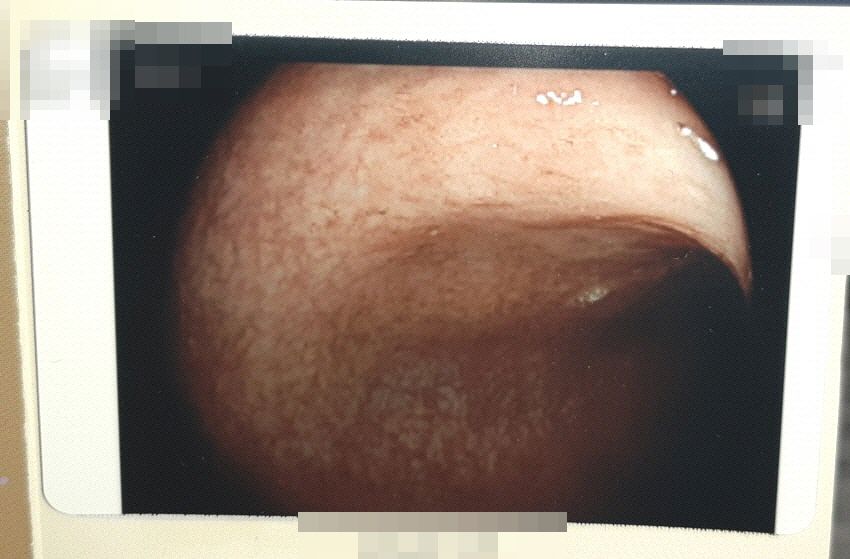

병원에서 준 사진 파일인데, 아마도 그 염증 부위를 촬영한 것 같은데,

어떤 상태로 판단되시는지 고견을 고하고자 합니다.

(제가 봤을 땐, 아마도 직장부위 인것 같은데,,)

• 1번 째 사진

대장의 염증은 장염 증상인 경우도 흔합니다. 비특이적인 염증도 많이 나오구요. 사진만 봐서는 염증성 대장 질환 같아 보이지는 않아요.

• 올리신 사진의 소견만 가지고 구체적인 판단을 내리기는 어렵지만 해당 사진을 통해서는 심각해 보이는 병변이 있어 보이지는 않습니다. 염증이 있기 때문에 혹시 몰라서 조직 검사를 의뢰하였을 가능성이 높아 보이며 궤양성 대장염이나 크론병 같은 문제가 실제로 있을 가능성은 썩 높아 보이지 않습니다. 그렇지만 정확한 것은 결국 검사 결과를 확인해 보아야 하는 수밖에 없겠습니다.